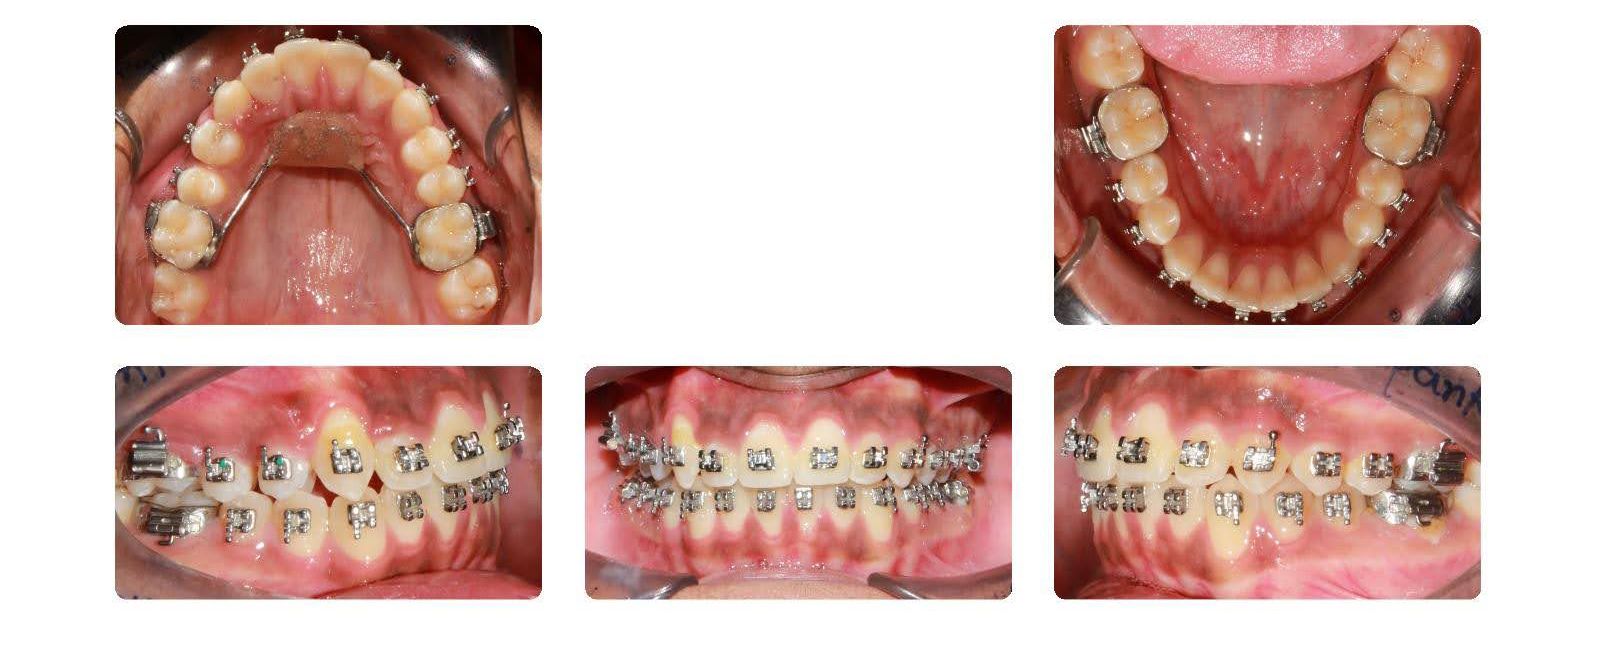

Patient's Gallery

Clinical case photos — click any case to open a larger view with title and description.